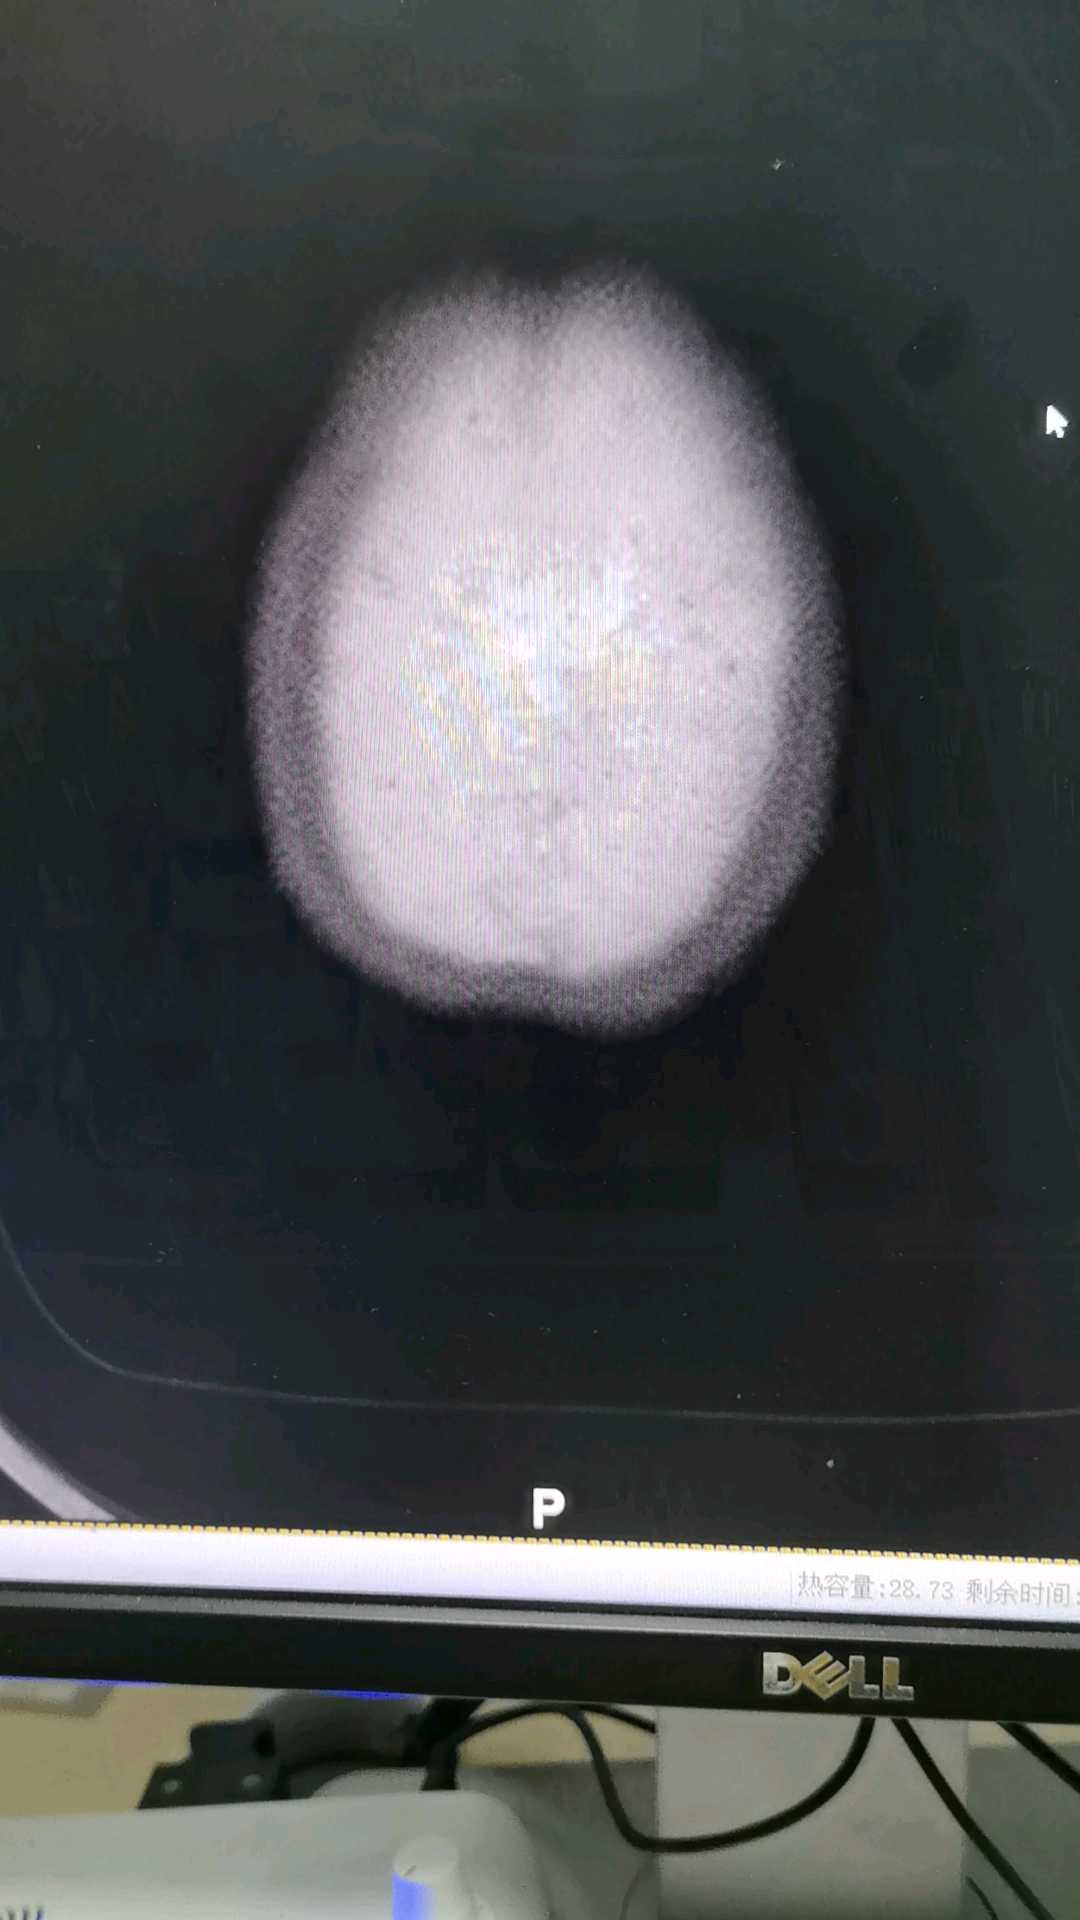

病例患者 女 73岁,头晕,来科室做的头部CT

患者 女 73岁,头晕,来科室做的头部CT